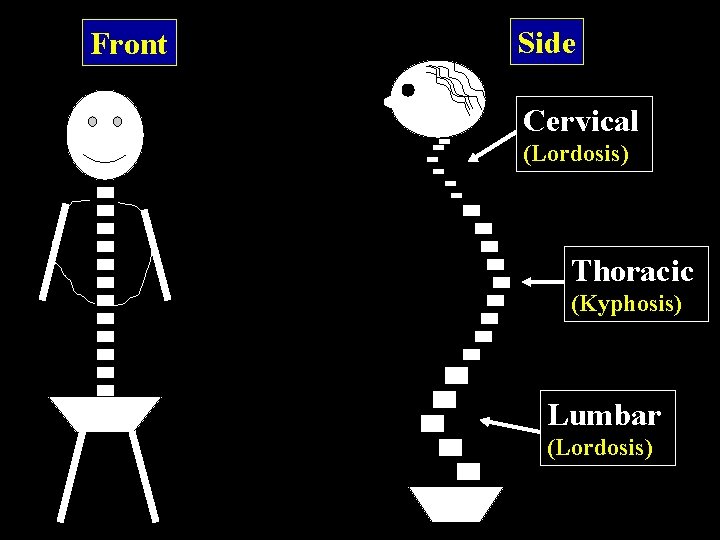

Front Side Cervical (Lordosis) Thoracic (Kyphosis) Lumbar (Lordosis)